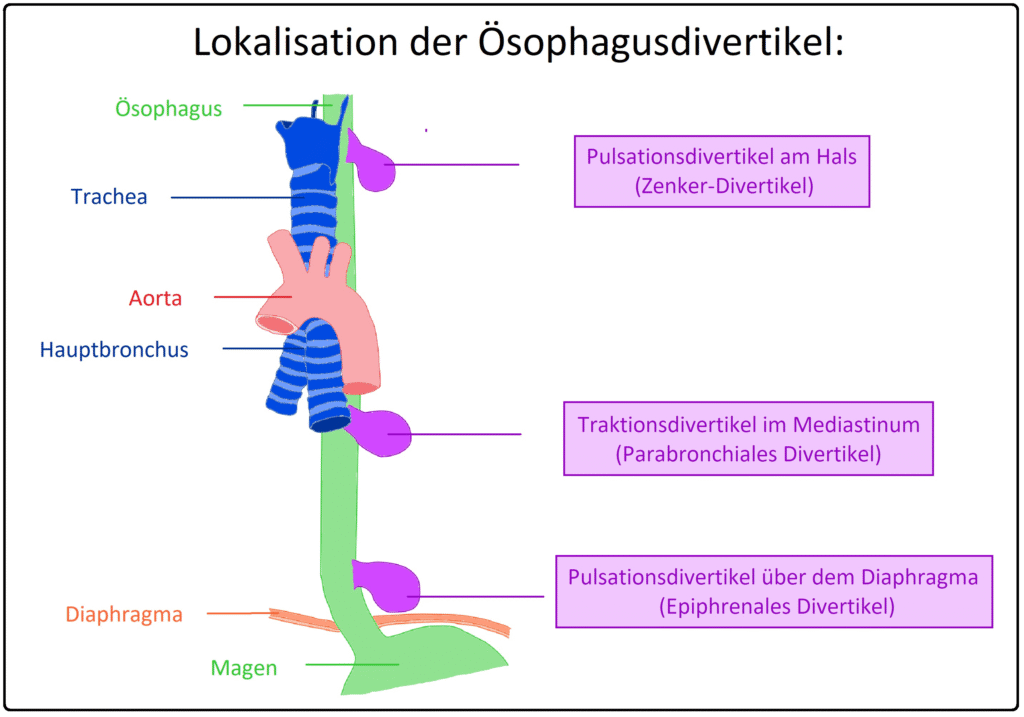

Ösophagus-Divertikel

Ausstülpungen der Ösophaguswand.

Typen

- Zenker-Divertikel (Pulsionsdivertikel, oben, Hypopharynx)

- Bifurkationsdivertikel (mittlerer Ösophagus)

- Entsteht durch Zug (Traktionsdivertikel, z. B. bei Lymphadenitis)

- Epiphrenisches Divertikel (distal, über Zwerchfell)

- Ursache: Motilitätsstörung (z. B. Achalasie) → Pulsionsdivertikel